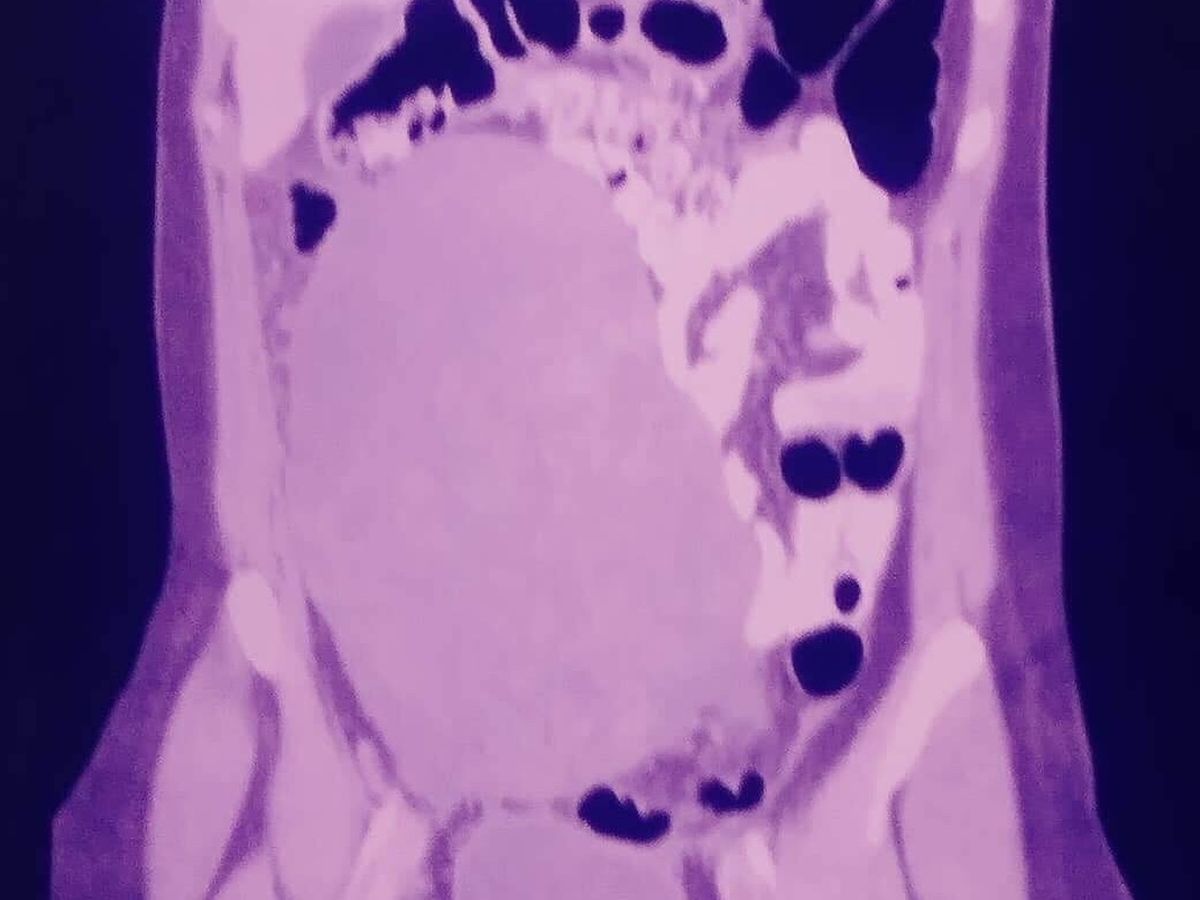

On March 11, I went to the hospital for both pelvic and abdominal pains that had been plaguing me for months. During this visit, I found out I had a large ovarian cyst--specifically, a teratoma--that had grown large enough to sit on the right side of my abdominal cavity after a CT scan.

On May 19, 2019, I went to the emergency room after a week with massive bloating, constipation, and a distended abdomen. In this visit, I got another CT scan and it became clear that not only do I have cancer but it is metastasizing.

My distended abdomen is also result of ascites flooding my abdominal cavity, which is both painful, and uncomfortable. It makes my my mobility limited, I can't sleep very well, and I struggle with day-to-day tasks.